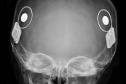

30/03/2026-Paraná assume liderança nacional em implantes de correção auditiva pelo SUS

Paraná assume liderança nacional em implantes cocleares pelo SUS